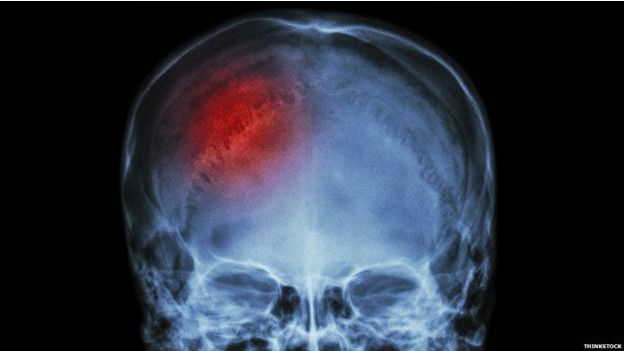

Ilustración de un derrame cerebral

Como todos los órganos, para funcionar bien el cerebro necesita el oxígeno y los nutrientes que lleva la sangre. El derrame cerebral se produce cuando se interrumpe ese flujo sanguíneo.

Esto puede suceder debido a un coágulo que bloquea el paso de la sangre o por la ruptura de un vaso sanguíneo en el cerebro.